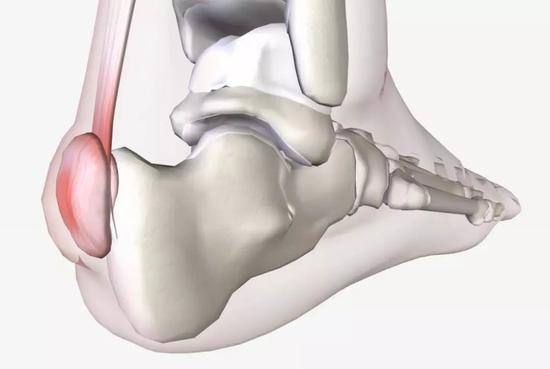

鲁普是在去年芝加哥马拉松赛后接受手术的,原因是他被一种名为 Haglund畸形 的跟骨疾病困扰。

Haglund畸形往往表现足跟骨的背面骨质凸起。

这个凸起恰恰可能与跟腱附着处产生应力集中现象以及摩擦,从而导致疼痛,这个疾病最早由帕特里克・哈格伦德(PatrickHaglund)医生于1927年发现,因此被命名为Haglund畸形。

如果保守治疗不能有效缓解疼痛,医生可能会建议手术切除骨嵴或修复跟腱。

Haglund畸形往往发生于先天遗传,这样的人群如果正常生活也许并不发生症状,但如果是运动员,需要反复牵拉跟腱,就容易导致畸形突出处与跟腱发生摩擦,严重时,甚至可以导致跟腱断裂。

Haglund畸形常常表现为跟骨结节后外侧的突出,往往合并跟腱滑囊炎。

这也导致Haglund畸形往往被诊断为跟腱滑囊炎,主要表现为脚跟处疼痛、局部肿胀。

跟腱两侧可见膨出,局部皮肤温度可升高,跟腱内外侧均可有压痛,被动背伸踝关节可加重疼痛。只有经过影像学检查,才能明确跟骨是否存在发育异常,